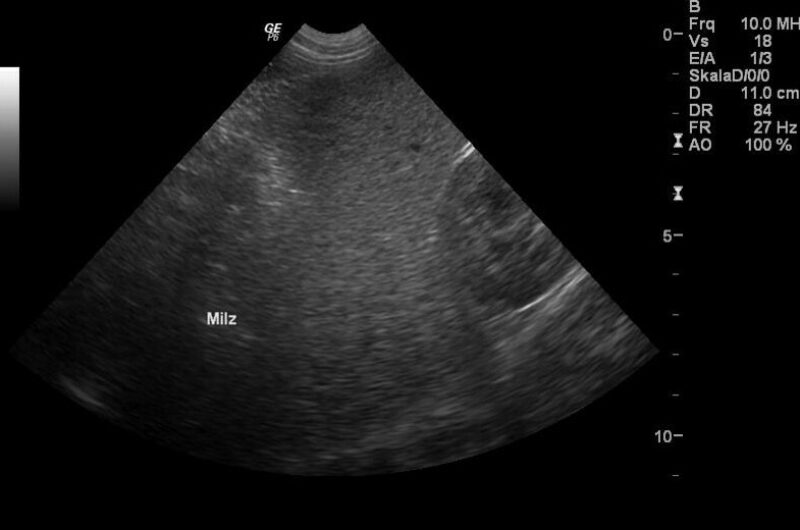

Die Symptome einer akuten Infektion können mild bis hochgradig sein und umfassen Apathie, Fieber, hämolytische Anämie und Thrombopenie. Begleitend können Hämoglobinurie und Ikterus auftreten. Hepatomegalie und Splenomegalie können vorliegen (Abb. 1).